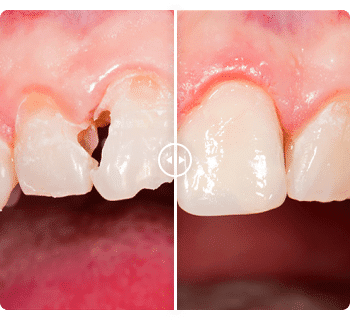

BEFORE AND AFTER

Before and after dental photos

To see what a smile makeover can accomplish, take a look

at our dentistry before and after photos.